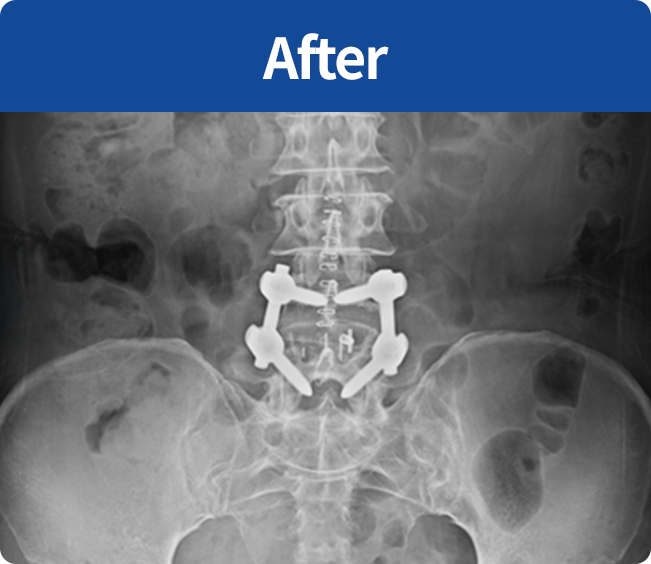

척추유합술

미세현미경을 통해 손상된 뼈와 인대조직을 제거하고 디스크의 역할을 해줄 인조 케이지를 삽입해

불안정한 척추체를 나사못으로 고정하는 수술 (척추 전방 골유합술, 척추 후방골유합술)